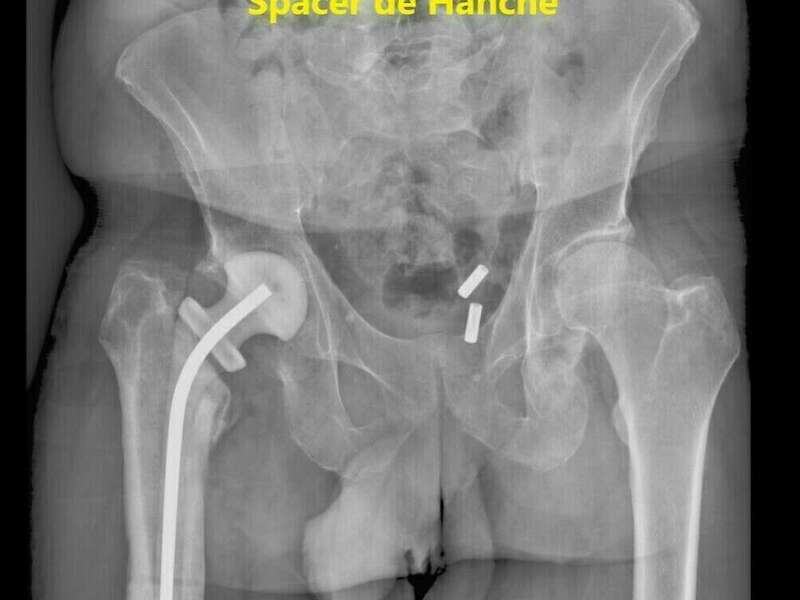

En cas d’infection tardive, la prise en charge varie d’une région à l’autre. Nous optons pour la solution en deux temps. Le premier temps correspond au retrait de l’ensemble des implants, à la réalisation de prélèvements microbiologiques, et à la mise en place d’un Spacer au ciment aux antibiotiques. Selon les constatations per-opératoires, le chirurgien décidera ou non d’introduire une antibiothérapie probabiliste avant d’avoir les résultats bactériologiques.

Un suivi clinique régulier permettra de vérifier l’amélioration clinique, la normalisation du bilan sanguin, et la tolérance aux antibiotiques. Le second temps aura lieu 6 semaines à 3 mois après le premier temps si le patient ne présente plus de symptômes et que son bilan biologique est normal. Le chirurgien reposera alors une nouvelle prothèse. L’antibiothérapie sera poursuivie après le geste chirurgical.